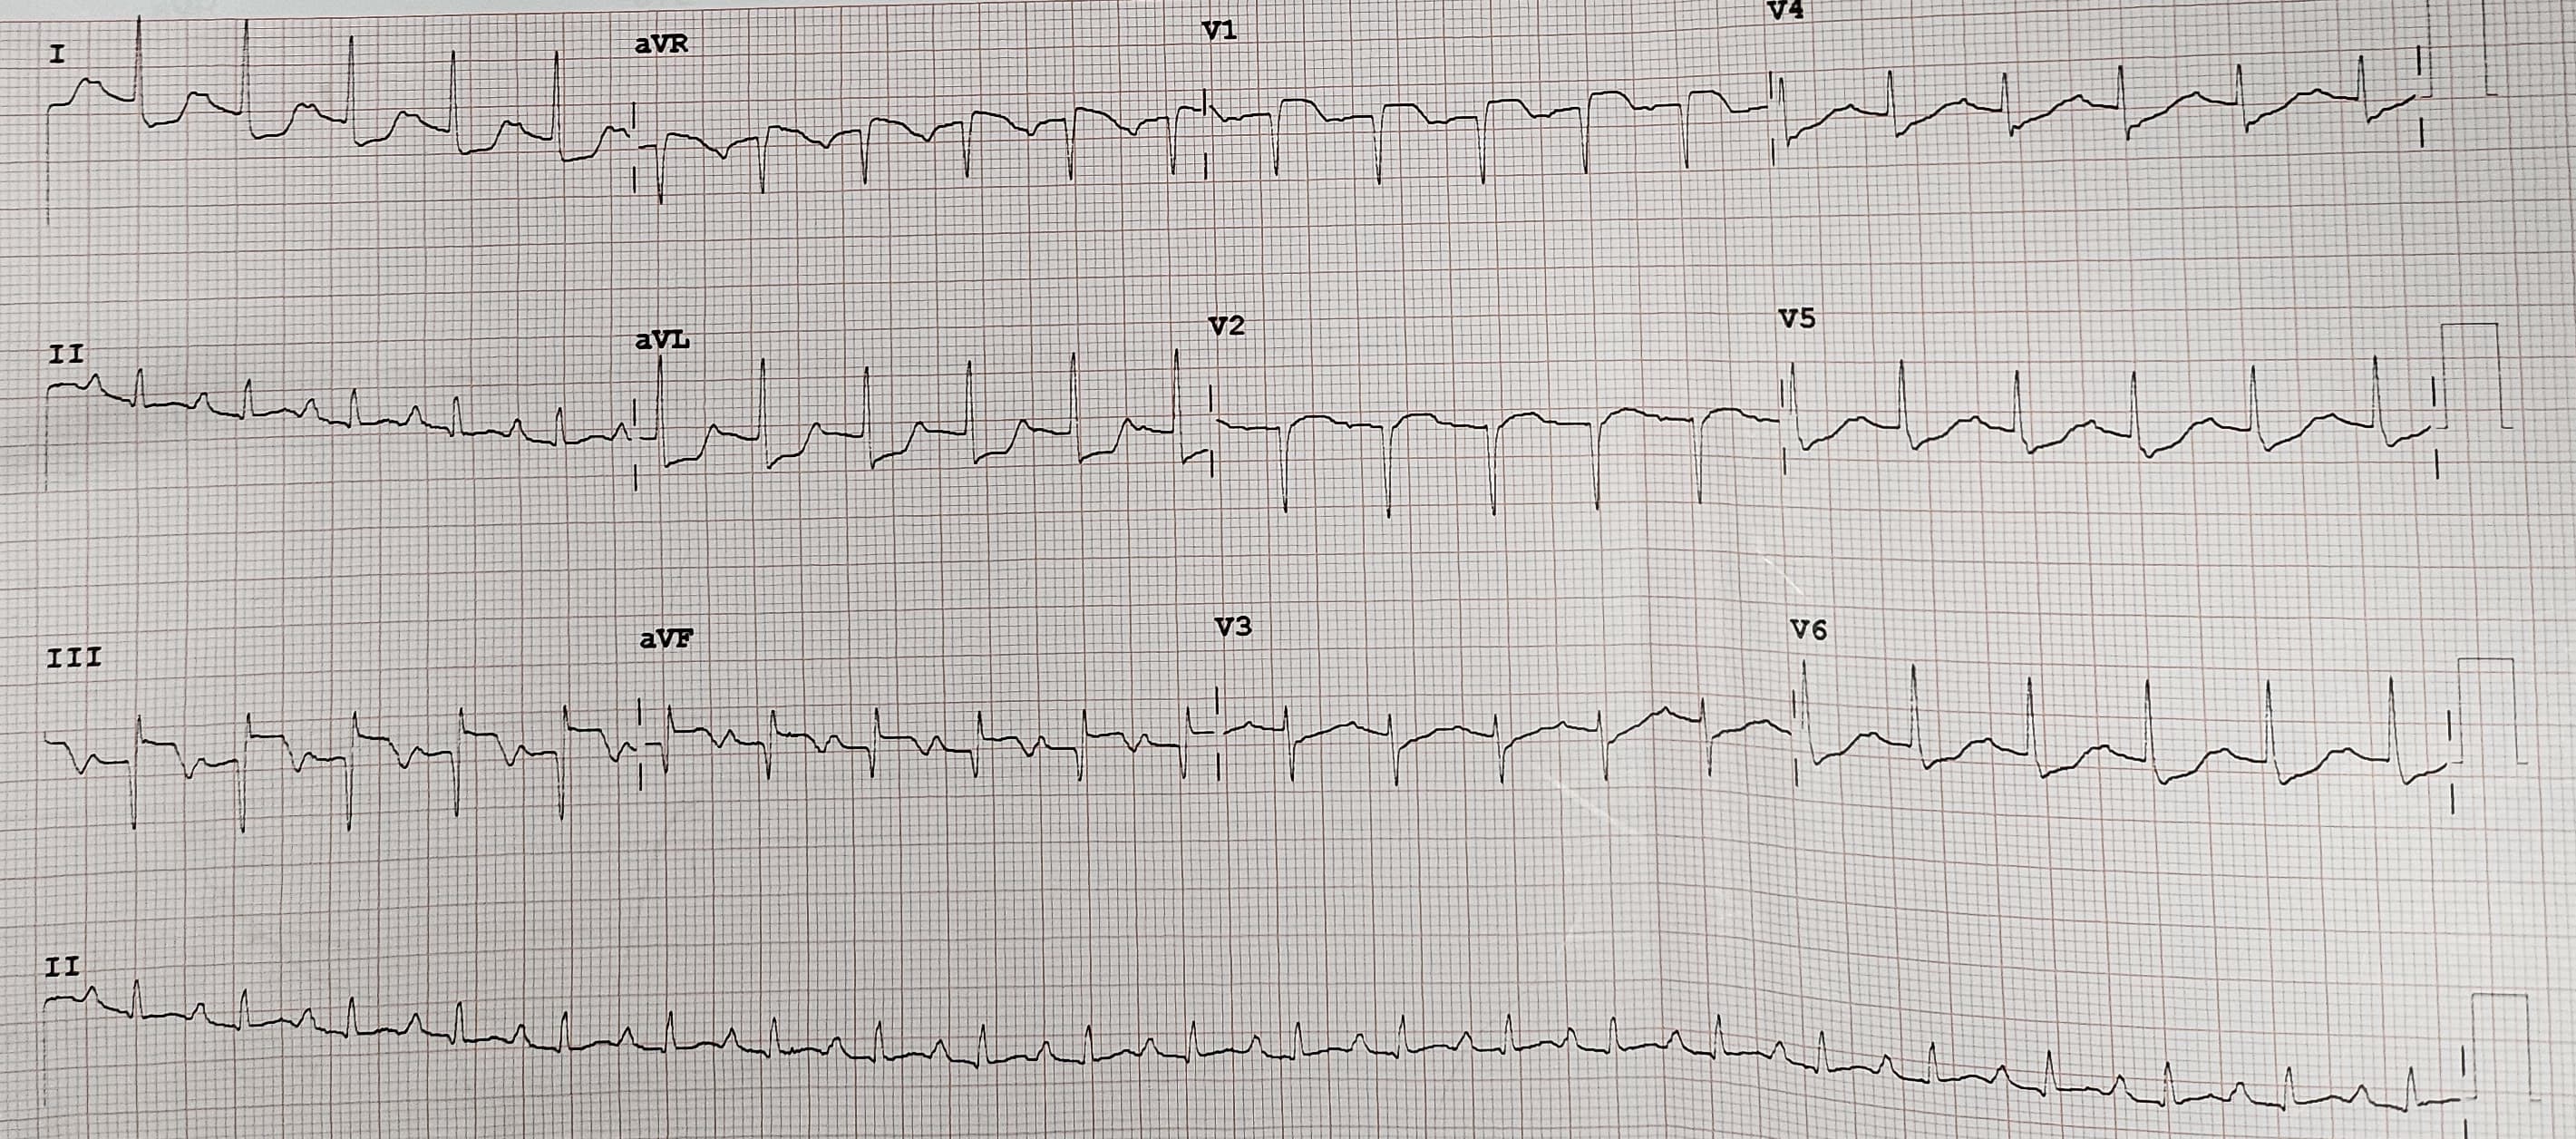

The electrocardiogram prior to catheterization procedure revealed sinus tachycardia with persistent ST-elevation and Q wave at lead III and AVF, ST depression at V4-V6, I, AVL. Echocardiography demonstrated good left ventricular function (LV EF 56%), reduced right ventricular function, global normokinetic and mild tricuspid regurgitation. Laboratory test result were unremarkable.